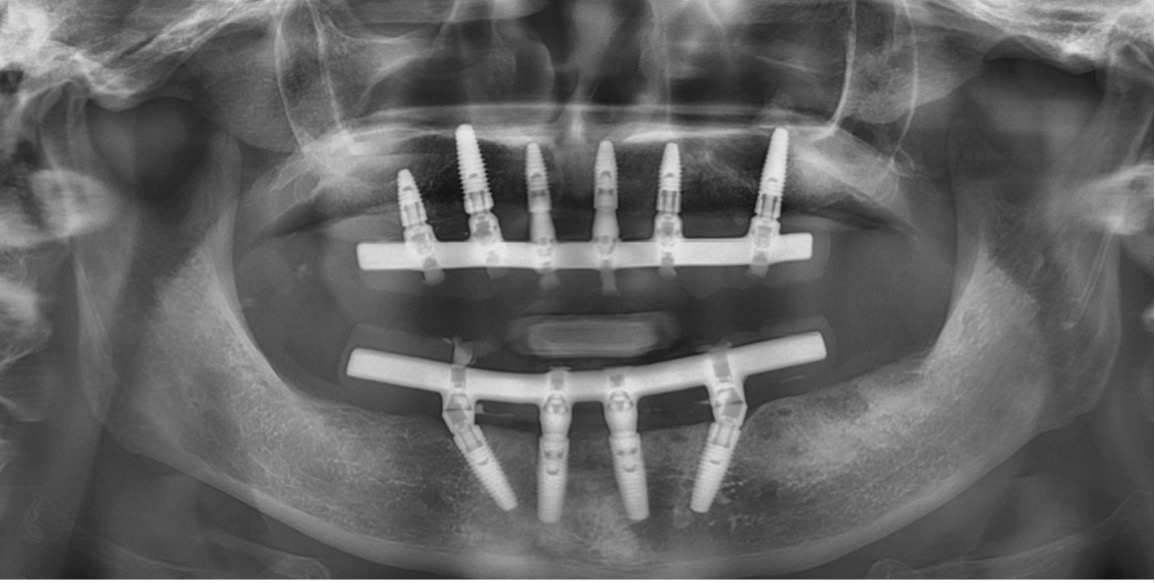

In some more complex cases, multiple implants are placed to support a bridge, or even more to replace someone’s entire dentition. This is referred to as the “All-on-4” procedure, where at least 4 implants are placed to provide them with a bridge that replaces all the teeth in one jaw, meaning 4 implants in the upper jaw and 4 implants in the lower jaw. The layman term for this technique is “Full mouth dentures.”